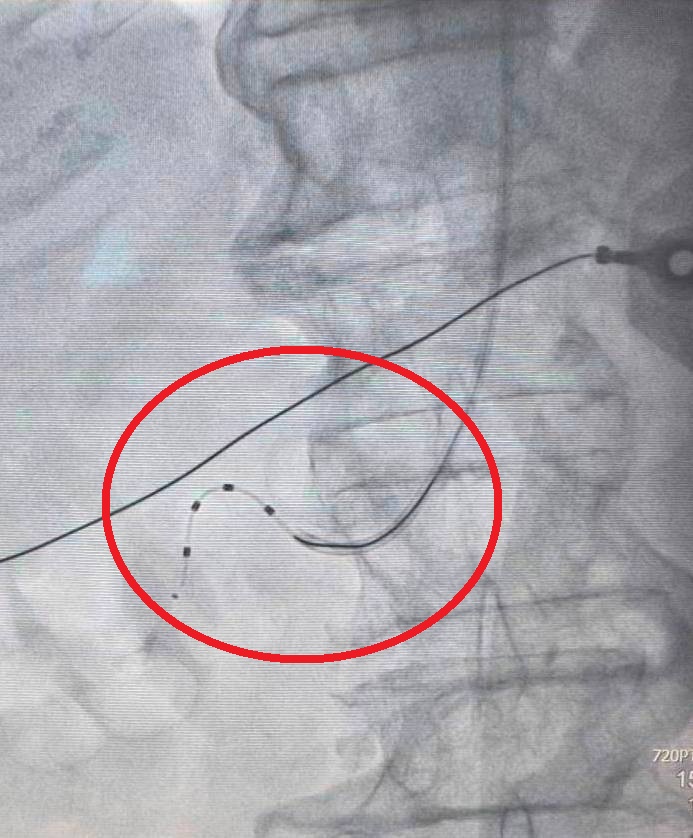

85歲病人血壓不穩定,以導管腎臟交感神經阻斷術降低腎交感神經活性(紅圈處)後,大幅改善狀況。

羅健賢醫師表示,導管腎臟交感神經阻斷術過程安全且時間短,病人恢復快、併發症少。